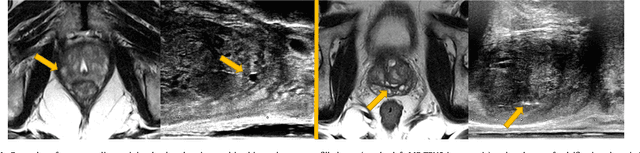

Abstract:One of the fundamental challenges in supervised learning for multimodal image registration is the lack of ground-truth for voxel-level spatial correspondence. This work describes a method to infer voxel-level transformation from higher-level correspondence information contained in anatomical labels. We argue that such labels are more reliable and practical to obtain for reference sets of image pairs than voxel-level correspondence. Typical anatomical labels of interest may include solid organs, vessels, ducts, structure boundaries and other subject-specific ad hoc landmarks. The proposed end-to-end convolutional neural network approach aims to predict displacement fields to align multiple labelled corresponding structures for individual image pairs during the training, while only unlabelled image pairs are used as the network input for inference. We highlight the versatility of the proposed strategy, for training, utilising diverse types of anatomical labels, which need not to be identifiable over all training image pairs. At inference, the resulting 3D deformable image registration algorithm runs in real-time and is fully-automated without requiring any anatomical labels or initialisation. Several network architecture variants are compared for registering T2-weighted magnetic resonance images and 3D transrectal ultrasound images from prostate cancer patients. A median target registration error of 3.6 mm on landmark centroids and a median Dice of 0.87 on prostate glands are achieved from cross-validation experiments, in which 108 pairs of multimodal images from 76 patients were tested with high-quality anatomical labels.

Abstract:Spatially aligning medical images from different modalities remains a challenging task, especially for intraoperative applications that require fast and robust algorithms. We propose a weakly-supervised, label-driven formulation for learning 3D voxel correspondence from higher-level label correspondence, thereby bypassing classical intensity-based image similarity measures. During training, a convolutional neural network is optimised by outputting a dense displacement field (DDF) that warps a set of available anatomical labels from the moving image to match their corresponding counterparts in the fixed image. These label pairs, including solid organs, ducts, vessels, point landmarks and other ad hoc structures, are only required at training time and can be spatially aligned by minimising a cross-entropy function of the warped moving label and the fixed label. During inference, the trained network takes a new image pair to predict an optimal DDF, resulting in a fully-automatic, label-free, real-time and deformable registration. For interventional applications where large global transformation prevails, we also propose a neural network architecture to jointly optimise the global- and local displacements. Experiment results are presented based on cross-validating registrations of 111 pairs of T2-weighted magnetic resonance images and 3D transrectal ultrasound images from prostate cancer patients with a total of over 4000 anatomical labels, yielding a median target registration error of 4.2 mm on landmark centroids and a median Dice of 0.88 on prostate glands.